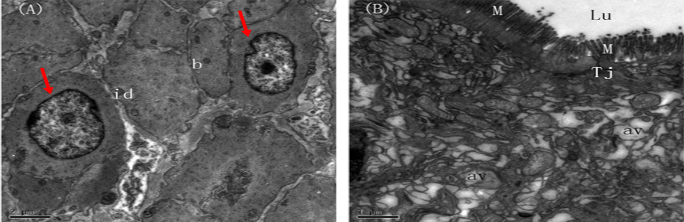

仔猪肠道粘膜透射电镜图